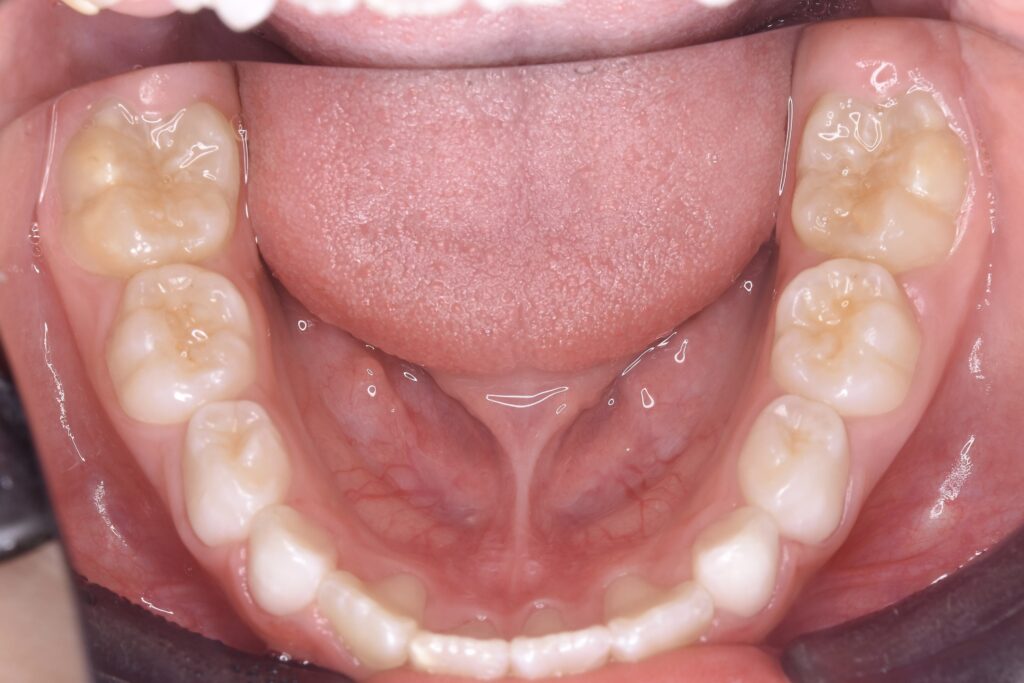

5歳 女児 小児矯正

歯並びの状態:

叢生(ガタガタ)

過蓋咬合(咬み合わせが深い)

AFTER

治療内容

上下の歯並びの幅を拡げつつ、前歯の関係を改善しました。

使用装置

急速拡大装置

リンガルアーチ

機能的矯正装置(マイオブレース)

治療期間

2年 + 後戻り止め期間(5年)